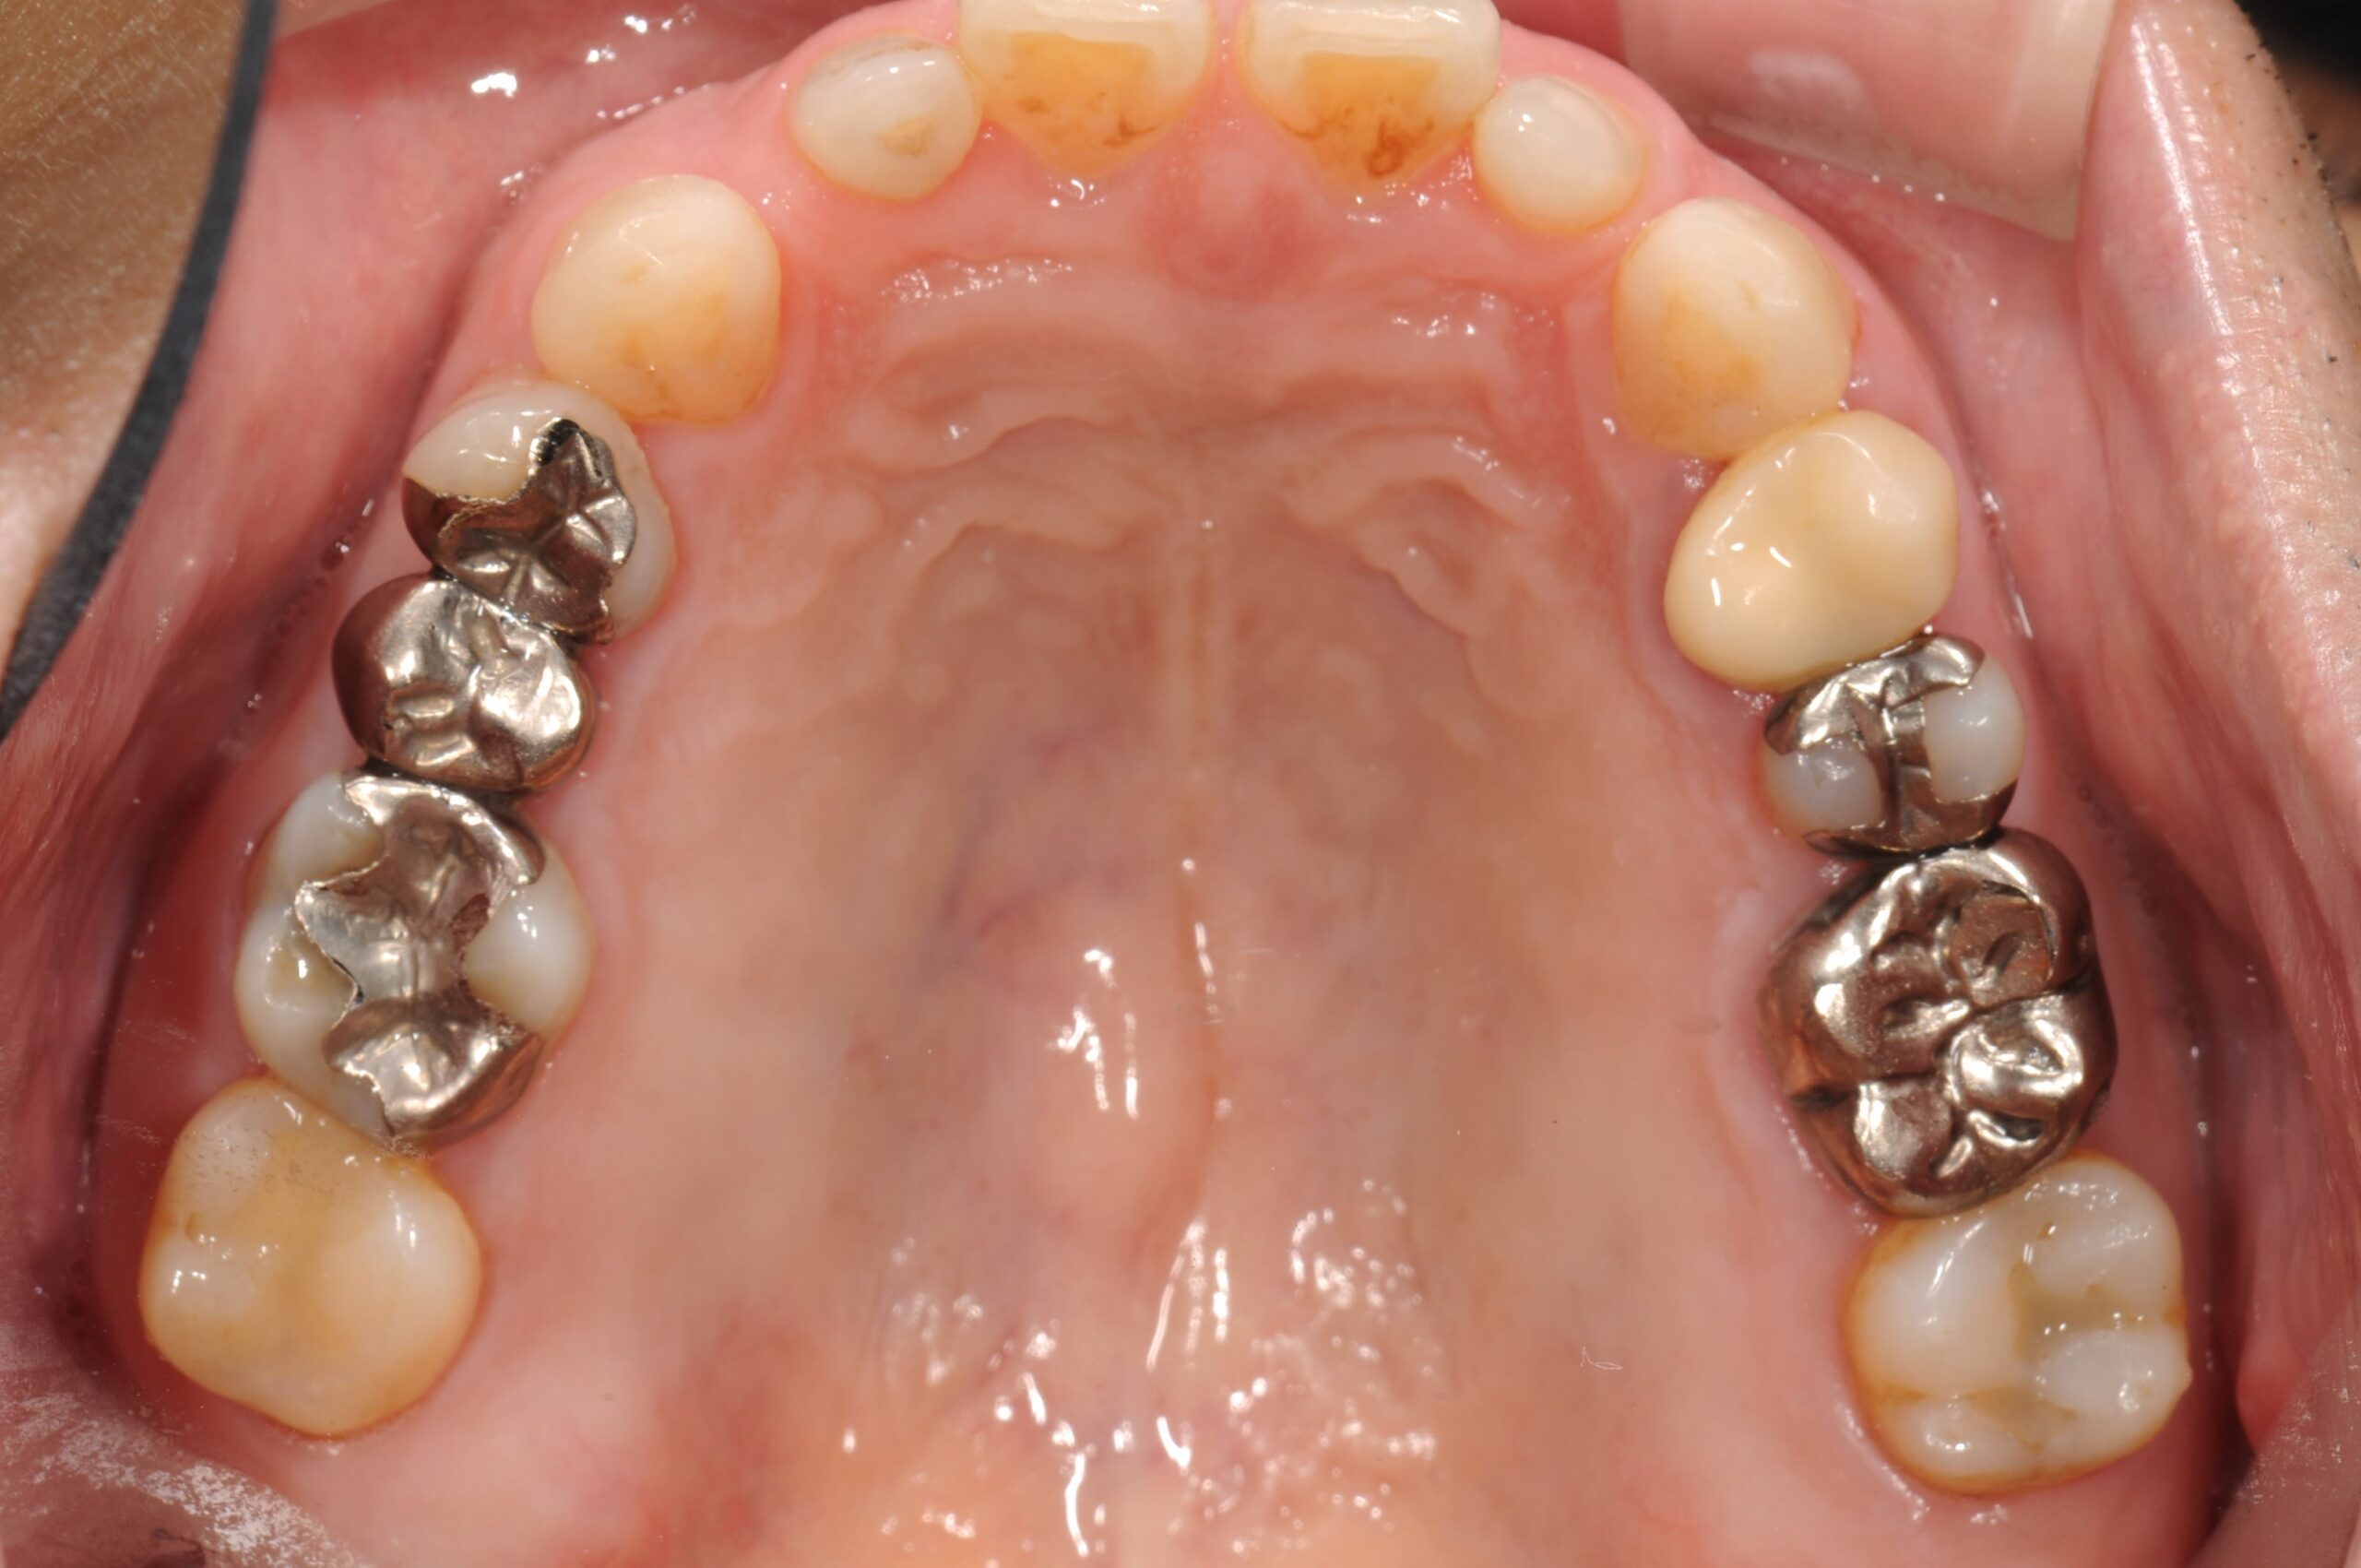

50代・男性

奥歯が欠けた|下顎左右6番の抜歯に伴うインプラント治療

before

治療前

症例写真 before

左右の下の奥歯が欠けたという主訴で来院されました。

診断の結果、下顎左右6番の根尖性歯周炎と2次虫歯が認められました。

どちらの歯も状態が悪く保存的処置が望めませんでした。患者さんとの相談の結果、抜歯しインプラントを埋入することになりました。

まず右下6番の抜歯、インプラント埋入手術、上部構造の装着を行い、次いで左下6番の治療を右下同様に進めました。

上部構造装着後10年以上経過しますが、定期的なメインテナンスと患者さんの日々のケアの甲斐あって、現在まで良好な経過をたどっています。